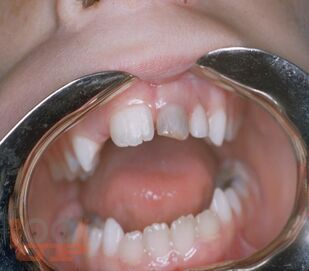

В пособии изложены сведения об анатомии периодонта временных зубов, этиологии, особенностях клинического течения, диагностике периодонтита временных зубов.